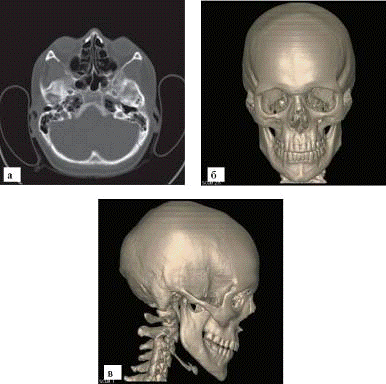

Рис. 5. МСКТ черепа: а - поперечный срез; б - трехмерная реконструкция, вид спереди; в - трехмерная реконструкция, вид сбоку ференцируются борозды оболочных артерий, каналы и звездчатые разветвления диплоэтических вен и пахионовых грануляций, а также пальцевые вдавления. Отдельные кости черепа соединяются между собой разного вида швами. В черепе ребенка места с неоконченным окостенением называются родничками.